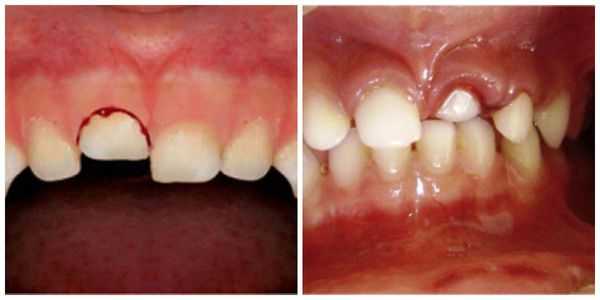

- Неполный вывих : боль усиливается при контакте с зубом, например во время приёма пищи; на слизистой оболочке полости рта имеются маленькие ранки, ссадины и гематомы; мягкие ткани отёчны; наблюдается смещение зуба в сторону и его значительная подвижность; вынужденное положение челюсти в связи с наличием болевых ощущений.

- Полный вывих: сопровождается сильной болью; зуб в лунке отсутствует; пустая лунка кровоточит; десна изменена в цвете; имеется припухлость; может возникнуть гематома; происходит локальное повышение температуры; некоторое время могут наблюдаться дефекты речи.

Неполный вывих характеризуется сохранением зуба в его лунке и сопровождается разрывом части волокнистых структур, окружающих и удерживающих зуб, либо растяжением волокон в той или иной степени. Для данной патологии характерно изменение положения коронки зуба и корня в зубном ряду по отношению к стенкам альвеолы. Зуб имеет неправильное положение вследствие смещения в вестибулярную ( в сторону губы) или оральную сторону, в сторону соседнего зуба или поворота вокруг оси. Это приводит к нарушению формы зубного ряда. Неполный вывих может сочетаться с переломом коронки, корня зуба или альвеолярного отростка.

Полный вывих характеризуется полным разрывом волокнистых структур периодонта (в том числе круговой связки зуба). При этом травмированный зуб в лунке отсутствует, а сосудисто-нервный пучок зуба всегда разрывается. Вывих может сопровождаться переломом края альвеолы. Иногда зуб может присутствовать в альвеоле за счёт единичных сохранившихся волокон круговой связки. По статистике полному вывиху чаще подвергаются фронтальные зубы верхней челюсти, реже — нижней. Меньше других подвержены полному вывиху клыки.